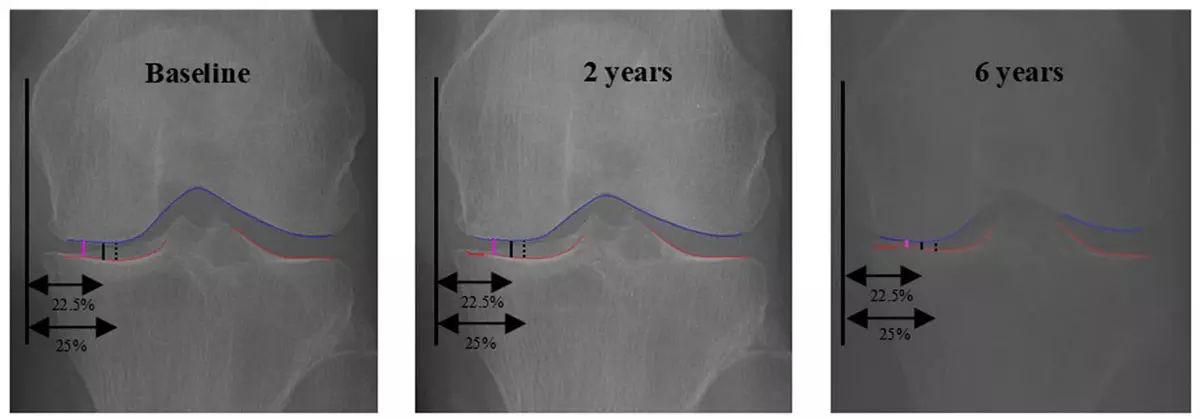

무릎 골관절염의 중증도는 보통 엑스레이에서 허벅지뼈(대퇴골)와 정강이뼈(경골) 사이의 간격(JSW)을 측정해 평가한다. 기존에는 관절의 특정 위치(JSW225, JSW250)를 고정해 간격을 쟀으나, 이는 환자마다 다른 해부학적 특성과 비대칭적인 마모 상태를 충분히 반영하지 못해 실제 마모가 심한 부위를 놓칠 위험이 있었다. 반면 이번에 개발된 oJSW는 AI가 관절 내부를 자동으로 탐색해 가장 좁은 지점을 수직으로 측정하므로 개인별 마모 상태를 정밀하게 반영한다.